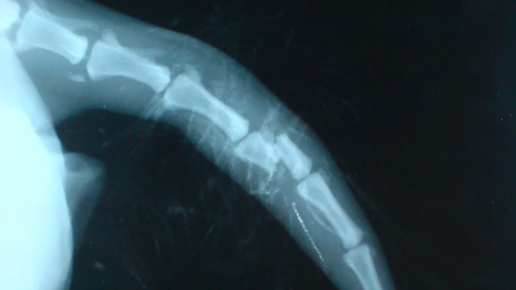

Собака сломала хвост: как помочь любимому питомцу?

Мы тщательно следим за состоянием своих питомцев, оцениваем дыхание, биение сердца, работу пищеварительной системы и состояние лап, но мало кто обращает внимание на хвост, а ведь он тоже может пострадать, что опасно для состояния животного. Ветеринарами диагностируются переломы, ушибы и вывихи хвостов, у котят и щенков может быть надлом, так как в этом возрасте костная система еще не сформирована окончательно. Проявляются все травмы отечностью, болью и нарушение подвижности. Но если ушиб может пройти...